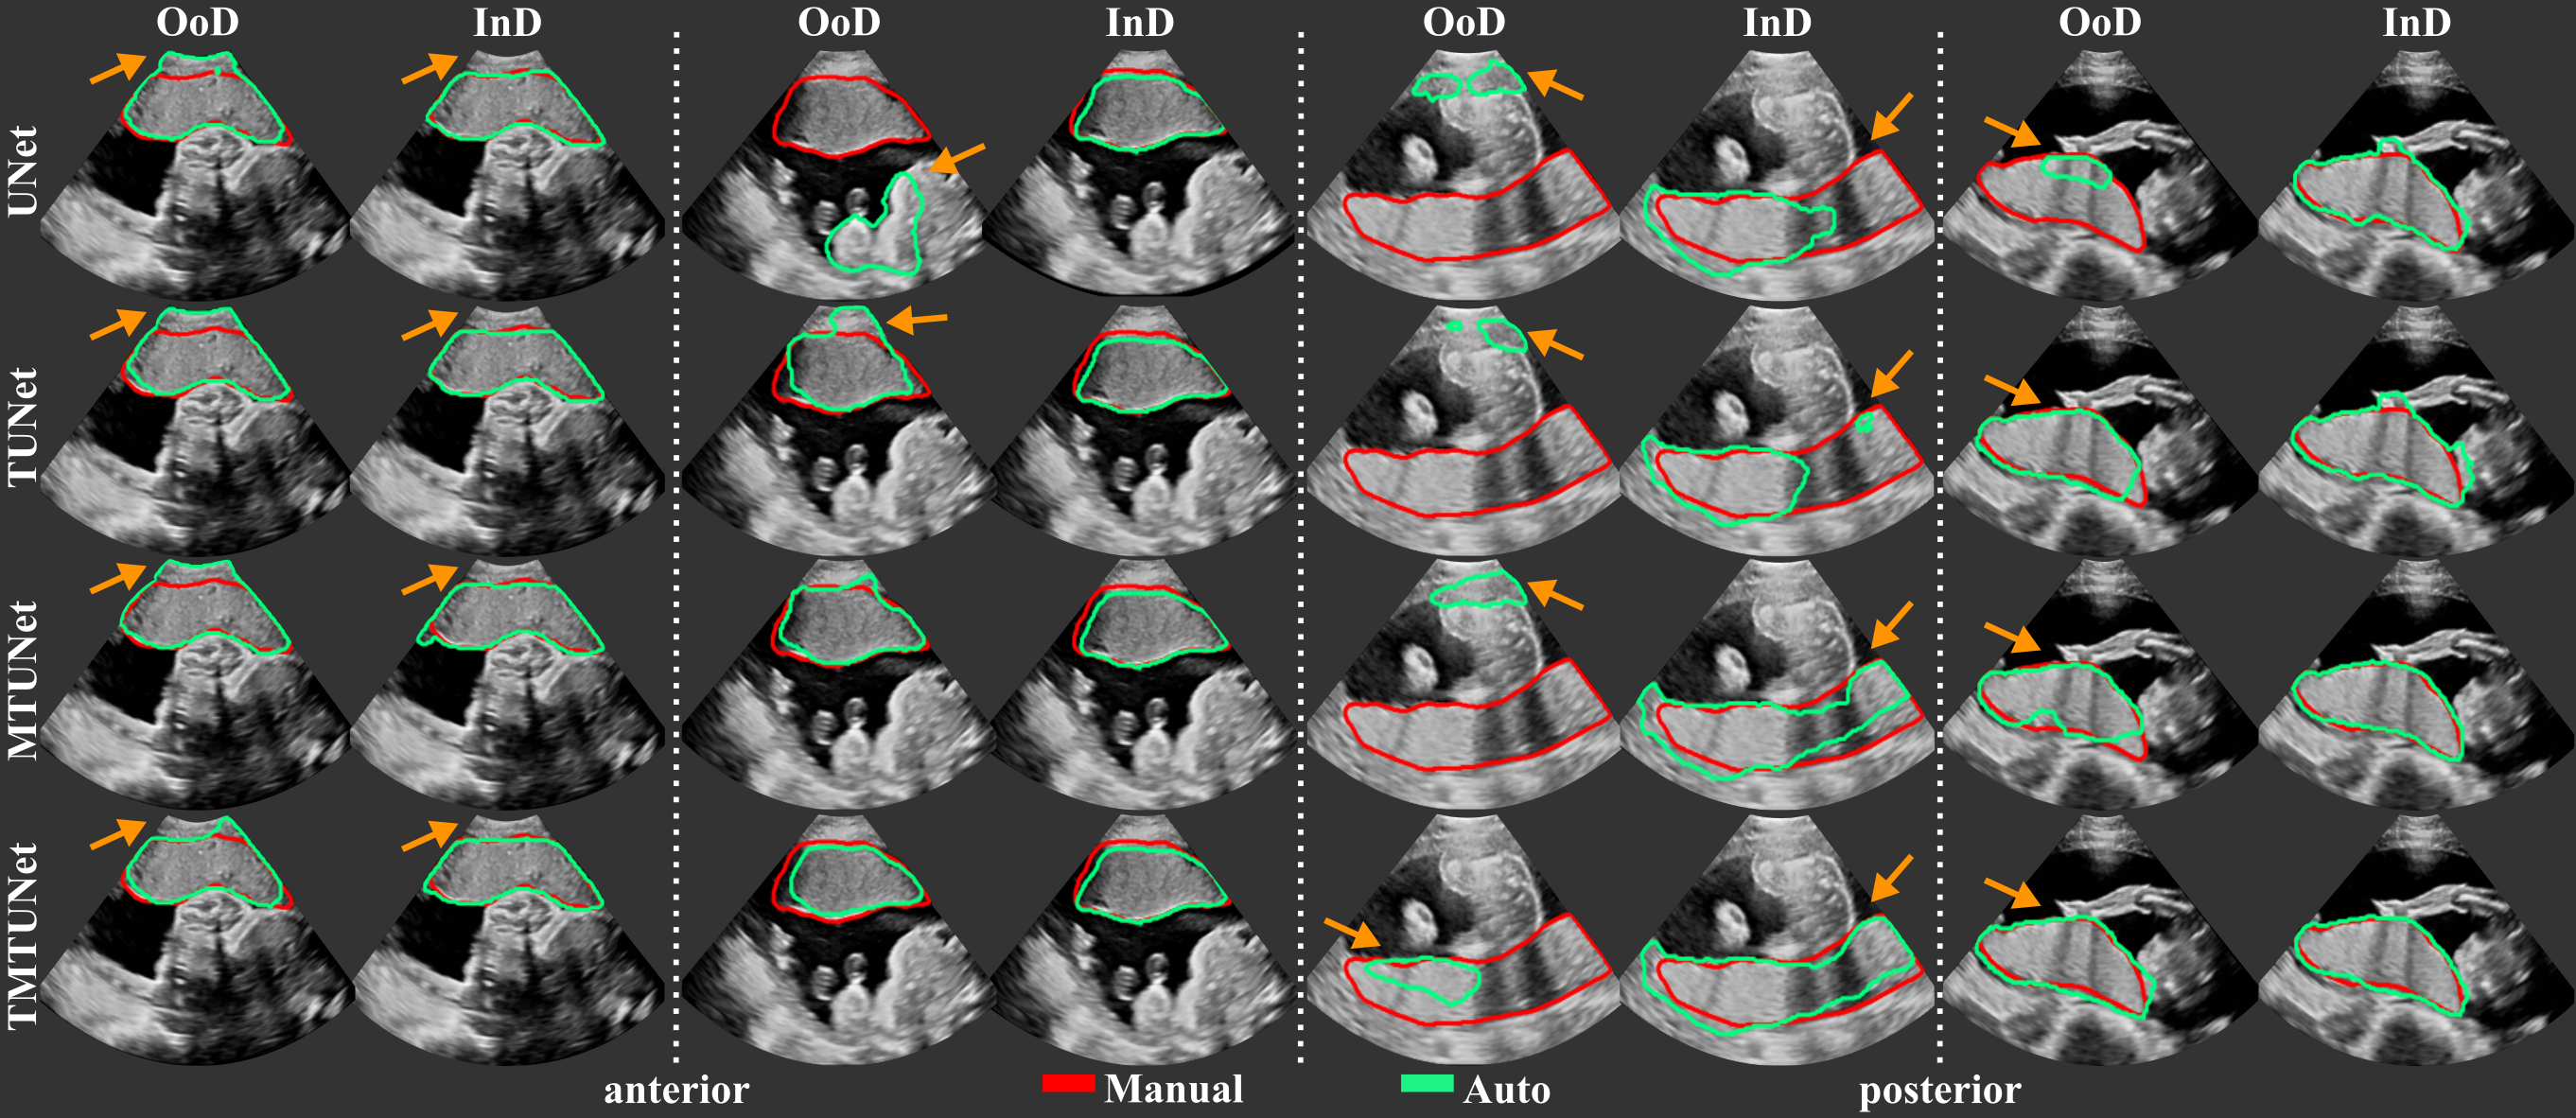

When the spatial transformation between multiple images is known, e.g., by using a multi-probe system as described in Sec. 2 for image acquisition, the segmentations in individual images can be combined to obtain the segmentation in the multi-view image. The multi-view segmentation performance is reported in Table 3 and representative results are shown in Fig. 5.

We observe that, in agreement with the results on single views, pre-training significantly improves the performance on OoD data, especially TMTUnet, showing a strong effect size. We would like to emphasize the performance increase on OoD data of TMTUnet trained on set P. Compared to the second best model, TUNet, the ASD is improved by 58.1% (11.81 mm to 4.95 mm) and the RHD by 34.8% (29.22 mm to 19.04 mm).

Interestingly, the performance on OoD data is in general higher on the multi-view data than on single view data. We emphasize here again that the segmentations are obtained from the single view image models and then fused for a multi-view image segmentation. The manual annotations are created on the fused images directly. We surmise that the increased performance measured on multi-view OoD data might be due to the artifact reduction in multi-view US.

For the majority of the performance measures, the multi-task model MTUNet performs best on both anterior and posterior placentas on the representative training set AP. This is statistically significant for the measures Dice, IoU and ASD with a moderate effect size.